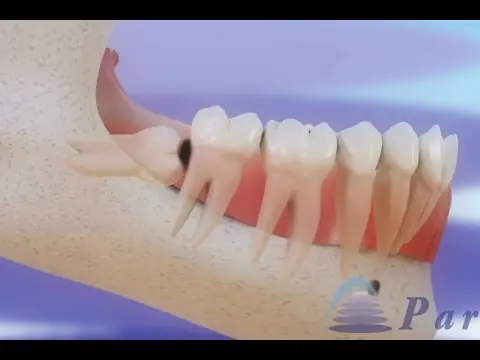

Esta semana hemos conocido una respuesta reveladora, aunque relativa a una estructura distinta: la muela del juicio, esa servidumbre estúpida de la biología humana, ese hueso inservible salvo para la catarsis y el tormento arbitrario, ese contradiós bucodental. El doctor Pangloss, cabe suponer, aduciría que la muela del juicio existe para consolar a los dentistas, y no han faltado biólogos que han encontrado en el último siglo respuestas similares, o similarmente vanas. Mi favorita: que una dieta cada vez más cocinada —tras la invención del fuego— redujo la necesidad del estupendo tercer molar de los homínidos. Pero no del primero y el segundo, parece ser.

La nueva investigación revela un mecanismo mucho más simple y verosímil: que la dentadura se construye siguiendo unos principios generales, leyes geométricas en el fondo, que rara vez están en condiciones de atender a los detalles poco relevantes. La muela del juicio no es un invento genial de Dios, ni de la selección natural darwiniana, para resolver un problema inexistente. Los mismos cambios en la geometría del cráneo que hicieron duplicarse al córtex cerebral —la sede de la mente humana— convirtieron el robusto tercer molar de los homínidos en una rémora para el homo sapiens.